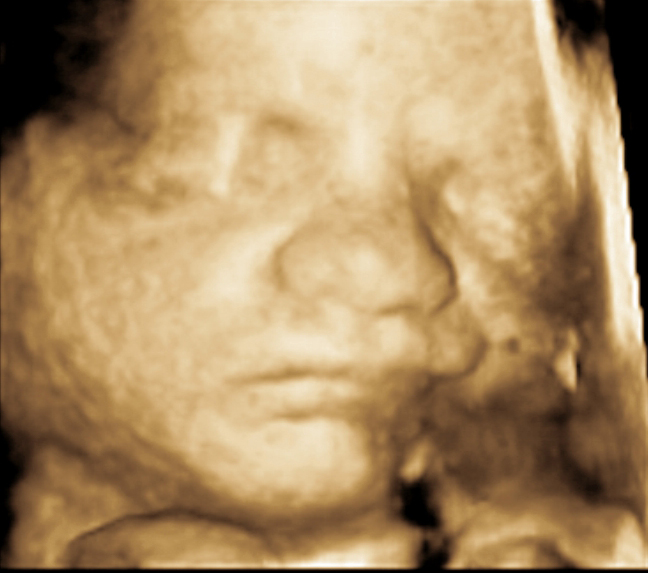

Magnetic resonance and ultrasound image . Da Form 5441 33 Download Printable Pdf Or Fill Online Evaluation Of Clinical Privileges Urology Templateroller